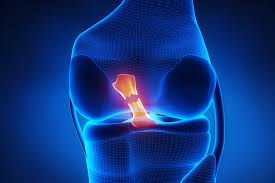

Anterior Cruciate Ligament Tear